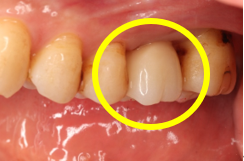

Before

初診時歯周ポケット6mm、左上4番に骨吸収を認める

切開はEPPT(entire papilla preservation technique)

エムドゲイン®サイトランス®を填入し、レーザーにて血餅形成、縫合

After

骨の再生を認める

歯周基本治療後に再評価し、ポケットが残存したのでEr:YAGレーザーを併用した歯周組織再生療法(エムドゲイン® 、サイトランス®を使用)を行ったケース

歯周病の好発部位である上顎第一小臼歯近心面における骨吸収に対して再生療法を行ったケース。一般的に根面溝という溝があり歯石の沈着が生じやすい。また溝の存在により術後に歯肉と歯根の付着が生じにくいため、今回はEr:YAGレーザーにて血餅形成を行い組織の安定化を図った。